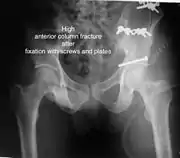

High anterior column fracture after fixation with screws and plates